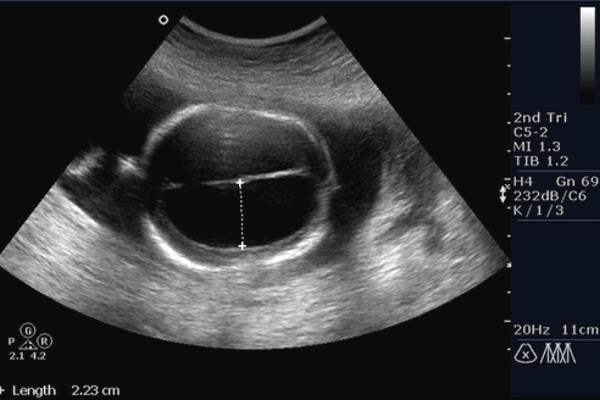

Опираясь только лишь на описание симптомов, нельзя точно диагностировать данное заболевание. Для того, чтобы сказать наверняка, нужно обратиться к врачу, который проведет ультразвуковое исследование и еще ряд других мероприятий, которые помогут установить точный диагноз. Каковы обязательные процедуры для диагностики заболевания?

- УЗИ органов малого таза.